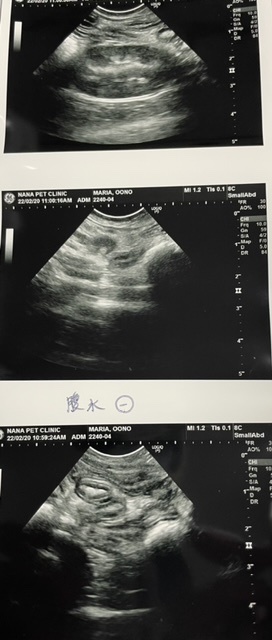

排便でもたまっているのですか?とお腹を見てもらいました。腹水です…エコーで見て頂き、腹水はFIP検査に。微熱、腹水ほぼFIPであろうとの診断でした

血液検査をし、こちらでもFIPウエットタイプ早期と診断されました

お腹は腹水でパンパンでした投薬開始日、今日から84日スタートです。

2月20日 血液検査

α1AG(炎症反応)が2000以上ですが、2週間後だとこんなもんですね。体調が良いようなので問題ないです。と協力病院の先生から言われました。

腹水はなくなっていました。